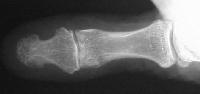

This incorporated, with some terminal resorption: